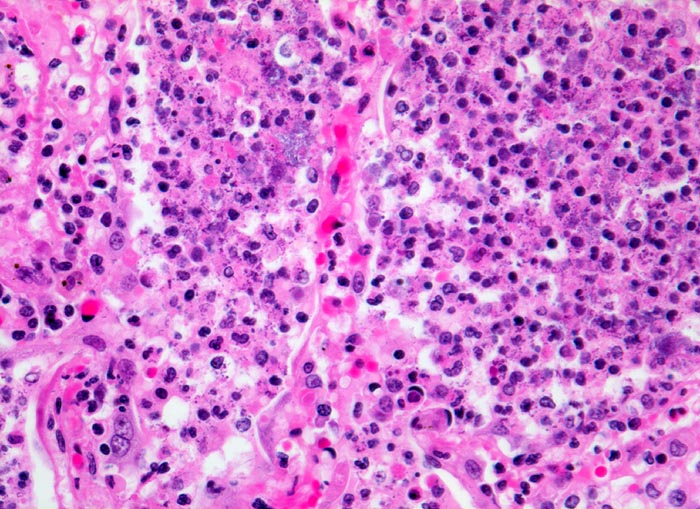

PathoPic ID 4652 - Bronchopneumonie: pneumonisches Infiltrat

Bronchopneumonie: pneumonisches Infiltrat

Entzündung infektiös

Lunge

Ausschnitt aus dem pneumonischen Infiltrat: die Alveolen sind gefüllt mit neutrophilen Granulozyten und feinkörnigen blauen

Bakterienhaufen.

Plötzlich einsetzende Symptomatik: hohes Fieber, Schüttelfrost, Husten mit Auswurf, allgemeines Krankheitsgefühl, Atemnot, Zyanose, Schmerzen beim Atmen, Nasenflügelflattern und Leukozytose.

Histologie

320